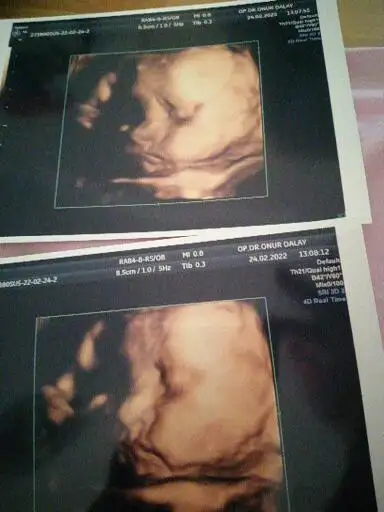

Bugün kontrele gittik. Çok şükür herşey yolunda. Rahim ağzı kapalı. Yeterli suları var. Ve gelişimleri gayet yerinde.

28 ve 29 cm. Geldiler. Kiloları da 603 gr ve 610 gram.

Bebeklerim den biri çok net gösterdi yüzünü. Renklide inanılmaz güzel göründü. Ama diğeri sürekli ellerini kapattı durdu. Görüntü alamadık.

Durum böyle. İşte bebişimin güzel fotosu